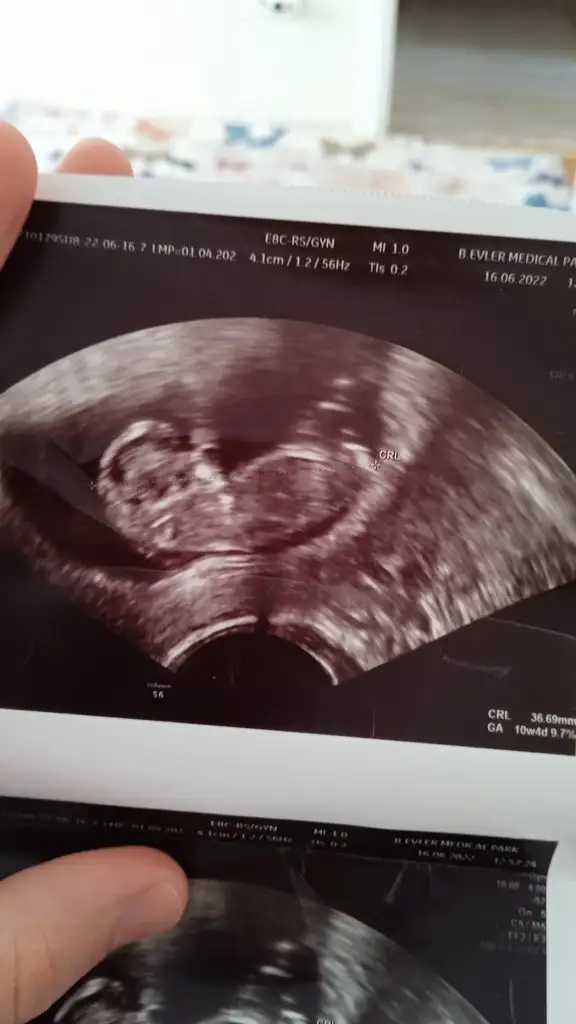

Kızlar merhaba karından ultrasonla bakıldı 10+6 cinsiyet tahmininiz nedir? 🤭 teşekkürler 🌸

• 18EE6BE5-7A40-45B3-9F6F-02162D0FD371.webp

18EE6BE5-7A40-45B3-9F6F-02162D0FD371.webp

11,7 KB · Görüntüleme: 67